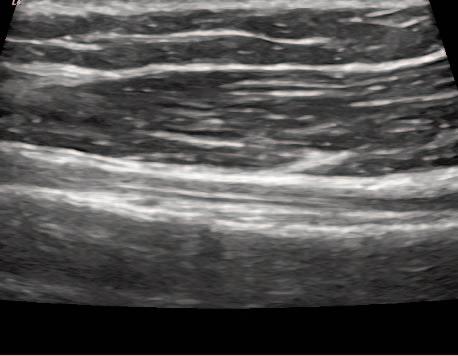

Figure 1a (left): Patient is seated with shoulder and elbow relaxed. Shoulder at 0 degrees of abduction, neutral rotation, elbow flexed and resting on leg or pillow with forearm supinated.

Transducer Placement: Short Axis (SAX). Probe placed transversely on the proximal anterior aspect of the shoulder, over the LHBT.

Figure 1b (right): Patient is seated with shoulder and elbow relaxed. Shoulder at 0 degrees of abduction, neutral rotation, elbow flexed and resting on leg or pillow with forearm supinated.

Transducer Placement: Long Axis View (LAX). Probe placed longitudinally on the proximal anterior aspect of the shoulder, over the LHBT.

Figure 1b.

Figure 2a: Normal Tendon-Short Axis View. LHBT is located deep within the inter-tubercular groove and viewed as a bright hyperechoic defined tendon. It is easily seen see between the bony greater and lesser tuber cles. The thin band of bright tissue overlying the top of the bicep’s tendon is the transverse humeral ligament.

Figure 2b: Normal Tendon-Long Axis View.

LHBT is seen running parallel along the image running proximal to distal from left to right. It should be seen as a bright hyperechoic fibrous band of tissue.The deltoid is seen above as a linear tissue with darker muscle bundles.